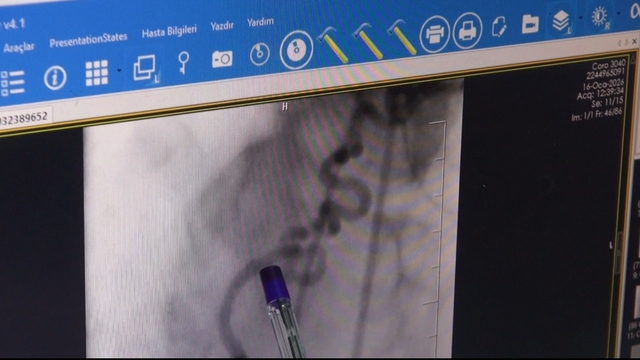

Batman’da yaşayan Şükrü Demirtaş, göğsünde yanma ve nefes darlığı şikayetiyle Batman Eğitim ve Araştırma Hastanesi Kardiyoloji Servisi’ne başvurdu. Yapılan anjiyoda kalbin sağ ana arterinden (RCA) köken alan ve akciğere uzanan anormal bir damar tespit edildi. Kardiyoloji Uzmanı Dr. Abdulaziz Taş ile Girişimsel Radyoloji Uzmanı Dr. Abdurrezzak Teken tarafından yapılan değerlendirmede, söz konusu damarın kalbe gitmesi gereken kanın bir kısmını ‘çalarak’ akciğere yönlendirdiği ve bu nedenle hastada göğüs ağrısı ile nefes darlığına yol açtığı belirlendi. Literatürde nadir görülen koroner çalma (steal) sendromu tanısı konulan hastaya işlem yapılması kararı alındı. Endovasküler yöntemle gerçekleştirilen embolizasyon işlemiyle, kalpten çıkıp akciğere uzanan ve kanı yönlendiren anormal damar başarıyla kapatıldı. İşlem sonrası hastanın şikayetlerinde belirgin düzelme sağlandı. Bu uygulamanın Batman’da ilk kez gerçekleştirildiği belirtildi.

Operasyonu gerçekleştiren doktorlardan Girişimsel Radyoloji Uzmanı Doktor Abdurrezzak Teken, “Şükrü amcamız bize 2 hafta önce kardiyoloji bölümüne başvuruyor. Aziz Hocam değerlendiriyor. Göğüs ağrıları ve nefes darlığı olması üzerine bir anjiyo planlıyor. Yapılan anjiyoda anormal bir şeyler görülüyor. Aziz Hoca beni çağırdı. Birlikte değerlendirdik anjiyoyu. Şükrü amcamızda sağ sistemden çıkan anormal bir üçüncü damar tespit ettik. Bu damar akciğere doğru uzanıyordu ve kalbe giden kanın bir kısmını çalıyordu. Ben ve Aziz Hoca işleme girdik. Anormal damarı başarıyla tıkadık. İşlem başarılı geçti. Şikayetleri göğüs ağrısı ve nefes darlığıydı. Amcanın bütün şikayetleri geçti. Bu da bize girişimsel radyoloji ile kardiyolojinin iş birliğinin be kadar önemli olduğunu gösterdi. Bu tarz vakalar 10 bin ile 100 bin de bir arasında görülebilen nadir vakalar. Batman'da açtığımız girişimsel radyoloji bölümü sayesinde bu tarz nadir vakaları da artık buralarda yapabiliyoruz. Sevkleri azalttık. Bu tarz işlemler için artık hastalarımız şehir dışına gitmeden Batman'da da tedavi olabiliyorlar" diye konuştu.